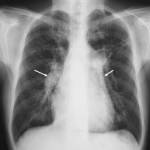

| F | Fields Fissures FB | • masses, consolidation, vessels, bronchograms • ?fluid in fissures, change of position • FB's- ETT, CVC, NG tubes, other |

| H | Hilar mediastinum | • LNs, Ca++, masses • widening - suggestion of dissection • displacement - suggestion of mass • angle of main bronchi - suggestive of collapse, masses • L hilum should NEVER be lower than R |